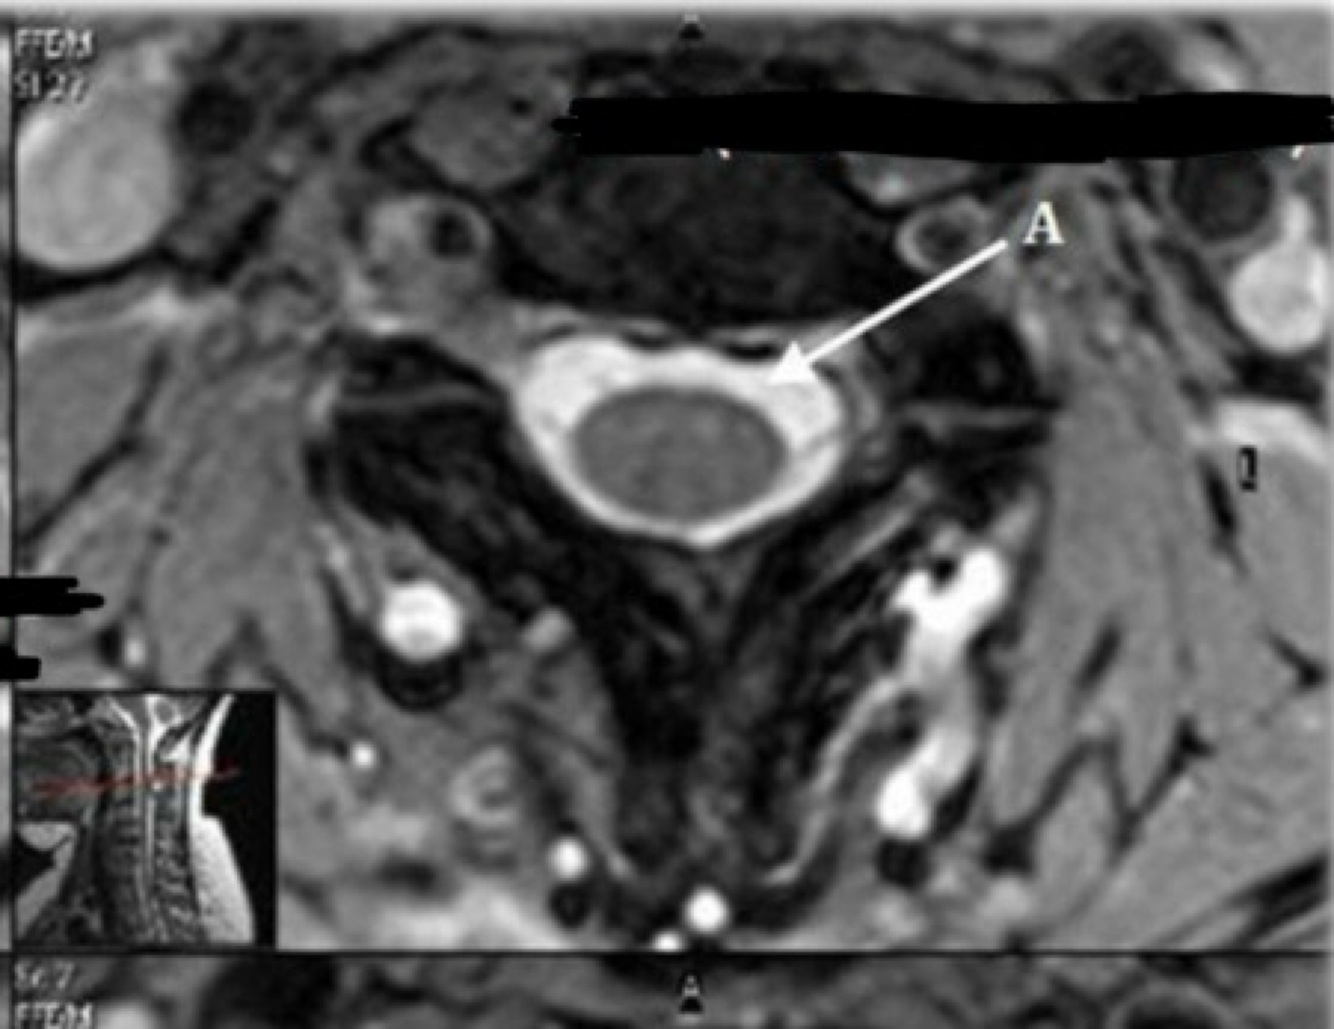

10

What is letter A?

A

CSF